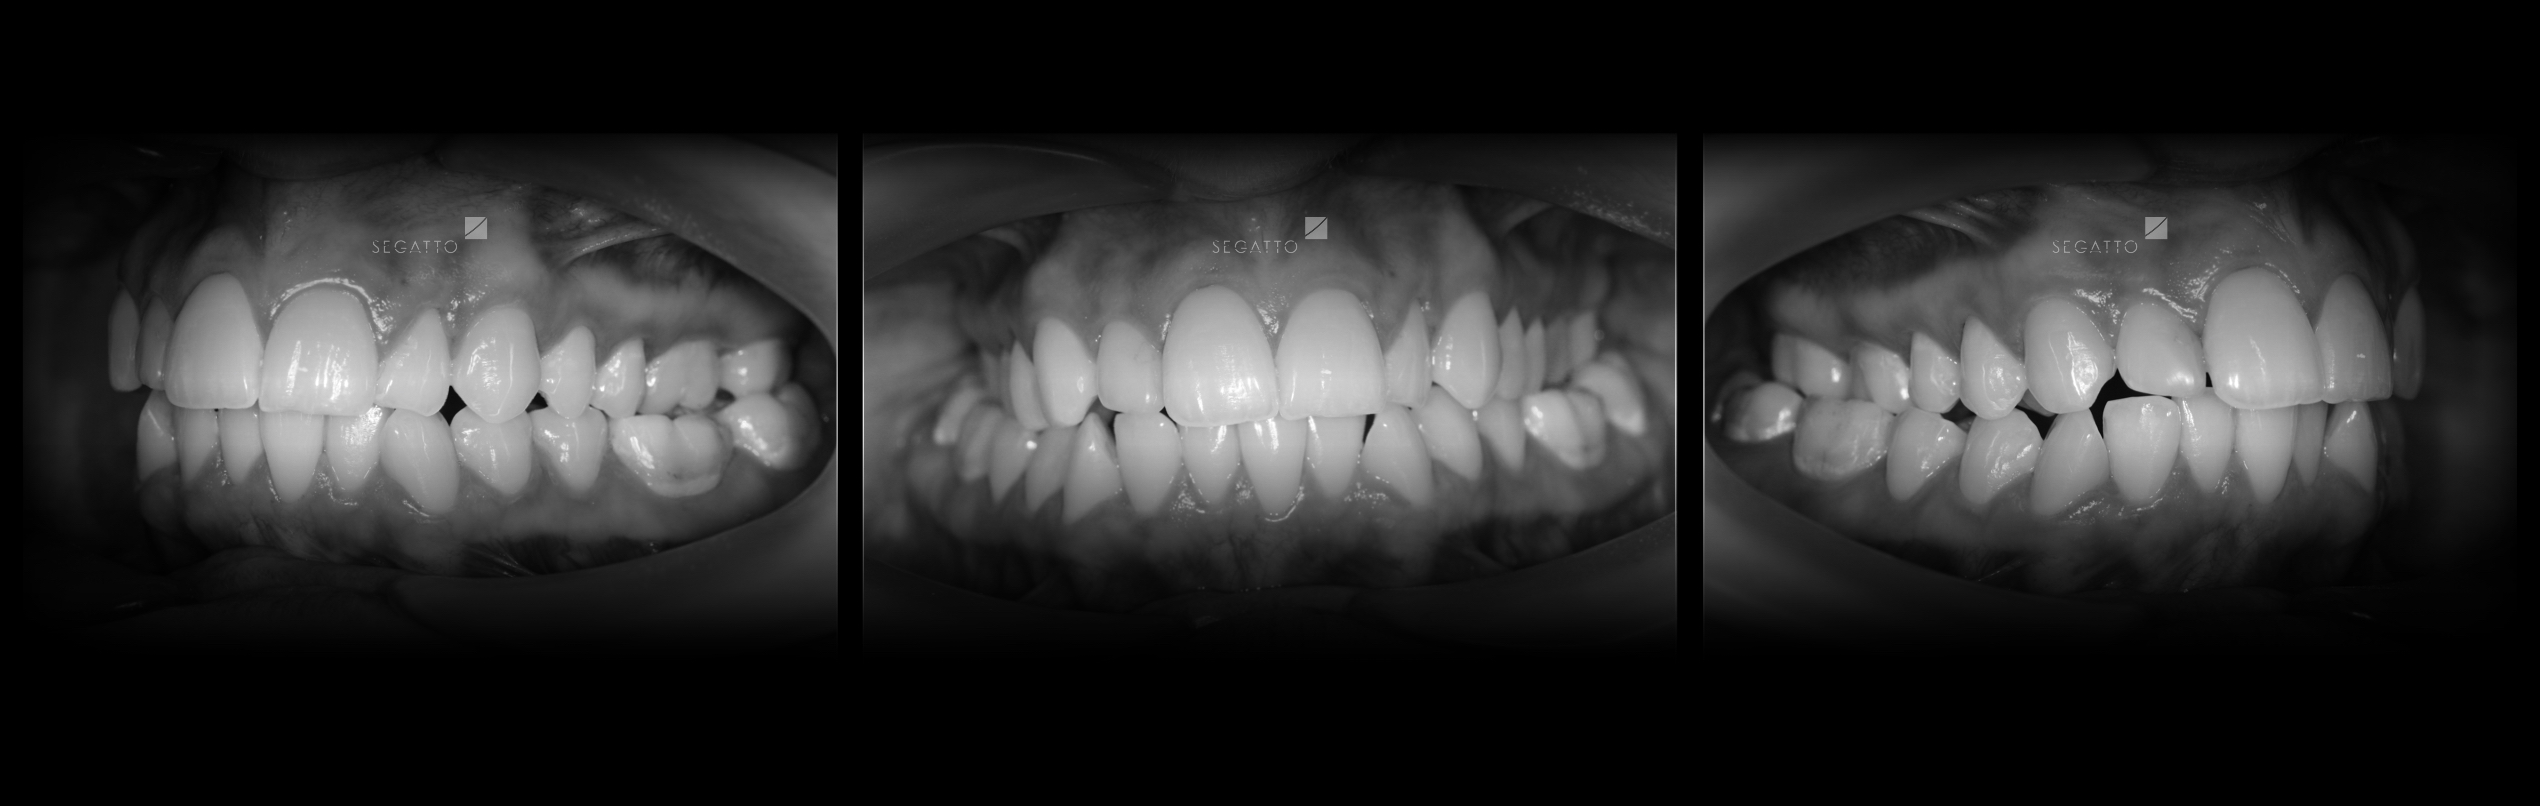

Orthodontics

Cases